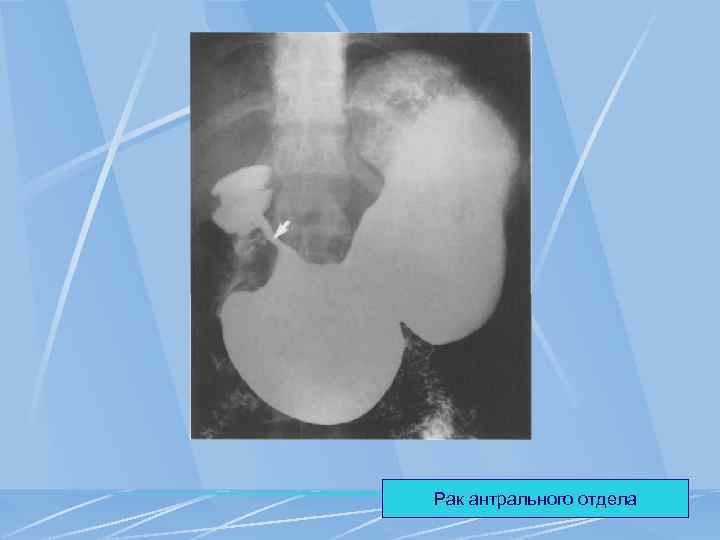

Рак антрального отдела